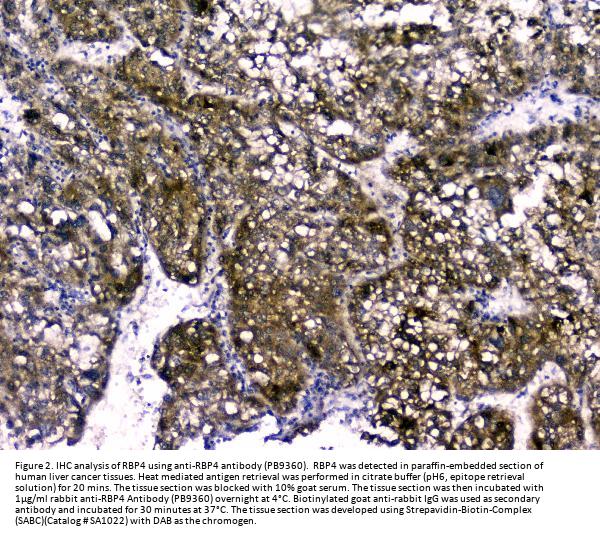

Immunohistochemistry (Paraffin-embedded Section), 2-5μg/ml, Human

RBP4 is also known as RDCCAS. This protein belongs to the lipocalin family and is the specific carrier for retinol (vitamin A alcohol) in the blood. It delivers retinol from the liver stores to the peripheral tissues. In plasma, the RBP-retinol complex interacts with transthyretin which prevents its loss by filtration through the kidney glomeruli. A deficiency of vitamin A blocks secretion of the binding protein posttranslationally and results in defective delivery and supply to the epidermal cells.

E.coli-derived human RBP4 recombinant protein (Position: E19-201L). Human RBP4 shares 86% amino acid (aa) sequence identity with both mouse and rat RBP4.

Boster Bio Anti-RBP4 Antibody Picoband® catalog # PB9360. Tested in ELISA, IF, IHC, WB applications. This antibody reacts with Human. The brand Picoband indicates this is a premium antibody that guarantees superior quality, high affinity, and strong signals with minimal background in Western blot applications. Only our best-performing antibodies are designated as Picoband, ensuring unmatched performance.